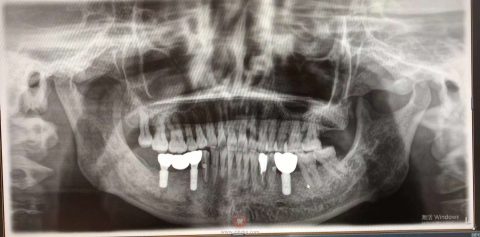

60多岁的许阿姨,在经历20余年的缺牙不适后,慕名来到杭州口腔医院未来科技城院区,经过童慧院长的全面诊断与设计,为患者做了种植修复。经过3个月的等待,阿姨今天终于戴上了牙,效果非常满意,对童院长赞不绝口。